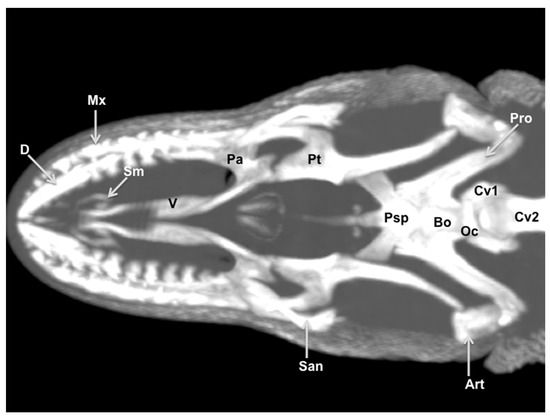

3.3. Maximum Intensity Projection (MIP) Images